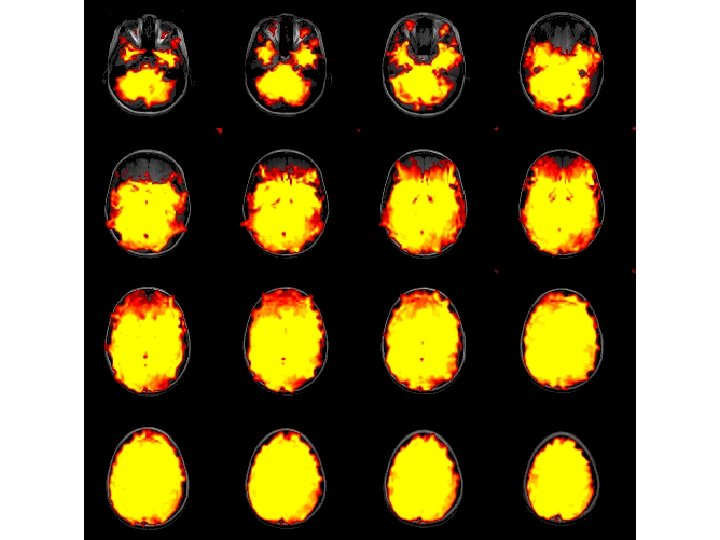

Standard Deviation Image